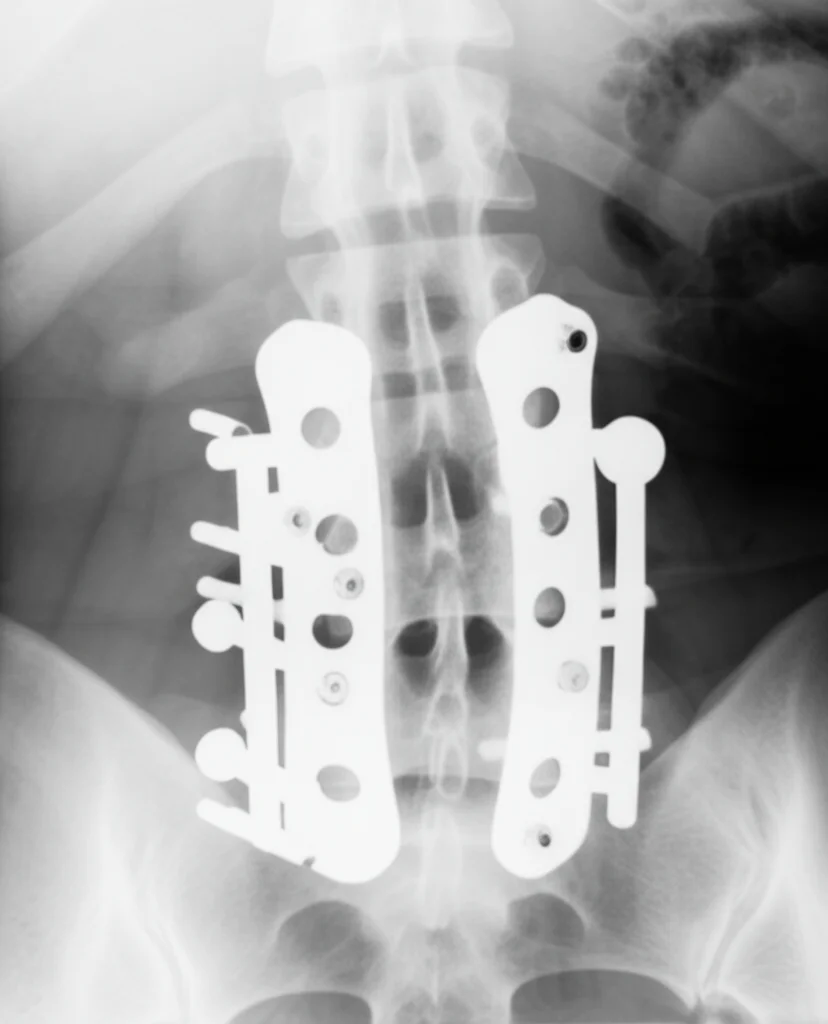

Ma come si stabilizza la vertebra dopo il taglio? Qui entra in gioco il Vertiwedge™. È un impianto spinale davvero particolare, progettato per essere inserito *dentro* l’osso della vertebra (intraosseo) nello spazio creato dall’osteotomia. Immaginatelo come un piccolo cuneo o spaziatore, stampato in 3D con una struttura che simula l’osso spugnoso, che aiuta a ripristinare l’altezza corretta della vertebra (fondamentale se c’è stato un collasso, magari per una frattura o per degenerazione) e a correggere l’allineamento. Ha una placca laterale integrata per il fissaggio con viti e, sul lato opposto, una sorta di “graffa” (staple) che si ancora all’osso per dare ulteriore stabilità. L’obiettivo? Ridare supporto strutturale alla vertebra, decomprimere il nervo e, soprattutto, preservare la mobilità naturale del segmento spinale.

Bello sulla carta, ma funziona davvero? Mantiene la stabilità e il movimento come promesso? Per rispondere a queste domande, è stato condotto uno studio biomeccanico molto interessante, e voglio raccontarvi come è andata. Abbiamo preso 8 colonne lombari umane da donatori (ovviamente nel pieno rispetto etico e normativo, si tratta di ricerca su campioni anatomici, non su persone viventi), da L1 a S1, di età compresa tra 35 e 75 anni, escludendo quelle con gravi patologie ossee, tumori o interventi precedenti.

Queste colonne sono state preparate rimuovendo i muscoli circostanti ma preservando tutti i legamenti e le strutture importanti per la stabilità. Poi le abbiamo montate su un simulatore spinale super avanzato, chiamato DISC (Dynamic Investigation of Spine Characteristics). Questo macchinario pazzesco permette di muovere la colonna in tutte le direzioni (flessione, estensione, inclinazione laterale, rotazione) e di applicare carichi di compressione variabili (da 0 a 500 Newton, che simulano le forze che agiscono sulla nostra schiena durante le attività quotidiane, come camminare o sollevare pesi leggeri), misurando con precisione le forze e i momenti risultanti.

Abbiamo testato ogni colonna in tre condizioni:

- Nativa (Native): Lo stato iniziale, prima di qualsiasi intervento, per avere un riferimento della sua biomeccanica naturale.

- Configurazione Completa (FullConfig): Dopo aver eseguito l’osteotomia sulla vertebra L4 e aver impiantato il Vertiwedge™ completo di viti e graffa stabilizzatrice, come da procedura chirurgica.

- Solo Viti (ScrewOnly): Disattivando la graffa stabilizzatrice, per capire quanto contribuisse alla stabilità complessiva (questa condizione è stata testata solo se la colonna reggeva bene il test precedente).